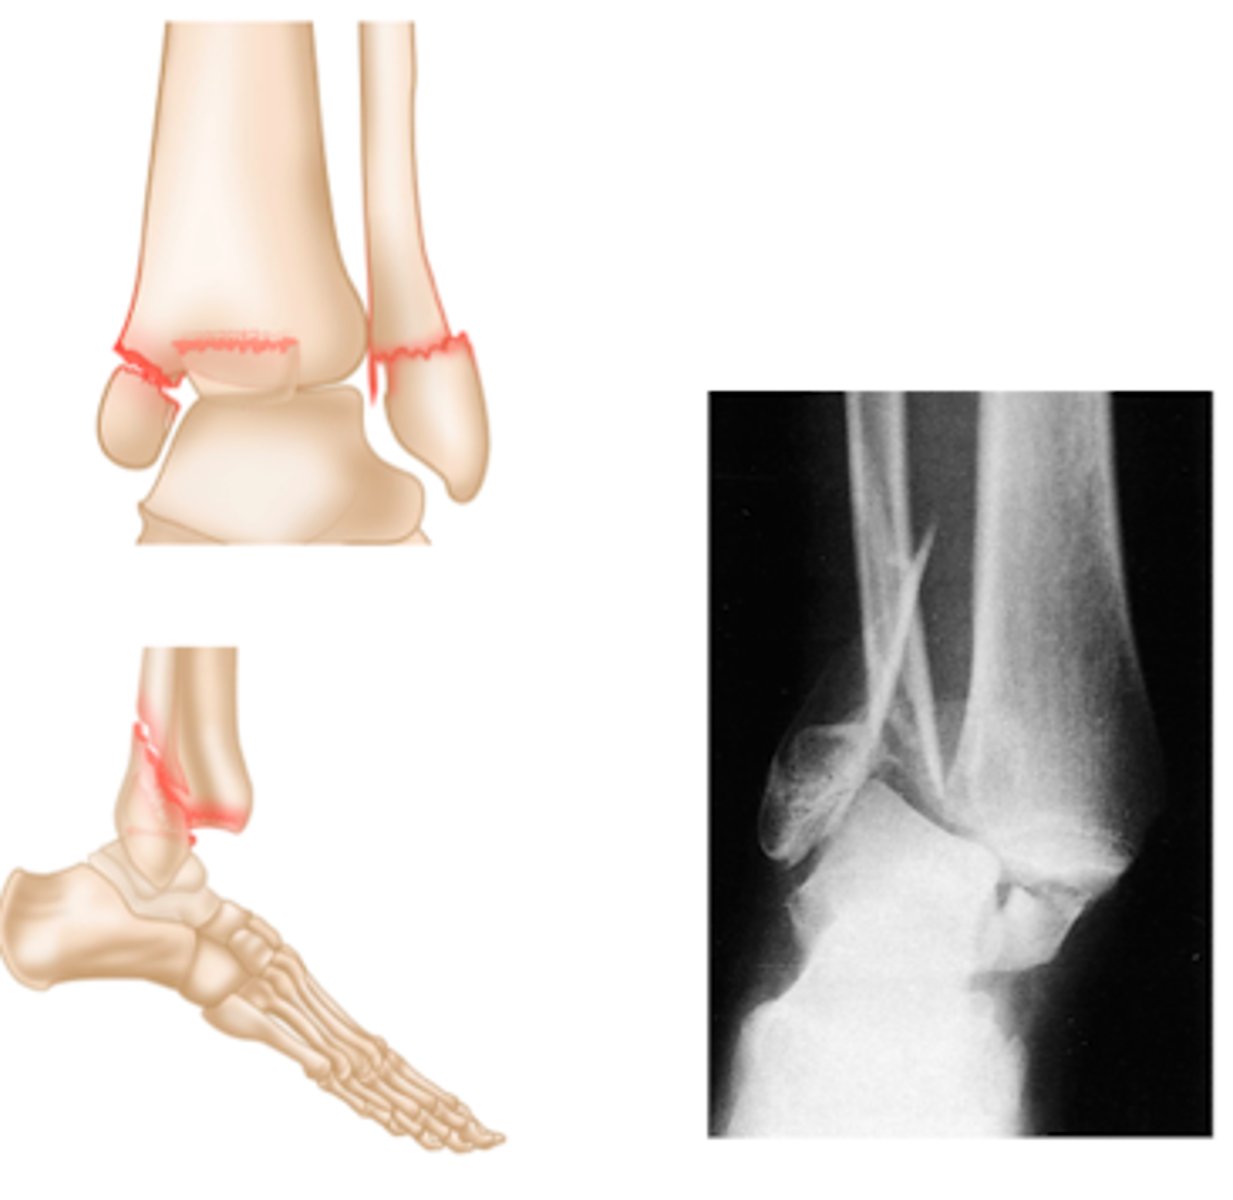

XR of Medial Malleolus Fx.

XR of Lateral Malleolus Fx with minimal displacement.

What is a bimalleolar ankle fracture?

involves BOTH the medial and lateral malleolus

What is a trimalleolar ankle fracture?

involves all THREE malleoli - medial, lateral and

What TWO movements can lead to a Maisonneuve fracture?

pronation

external rotation

What TWO fractures occur together in a Maisonneuve fracture?

Fx of medial malleolus

Spiral fracture of the fibula

What TWO XR findings are consistent with a Maisonneuve fracture?

Tear of the tibiofibular ligament

Widening of the ankle mortise medially